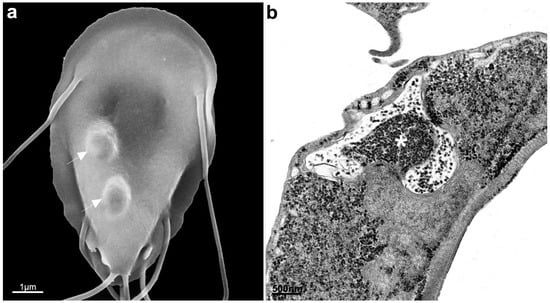

2.1. Trophozoite

2.2. Cyst